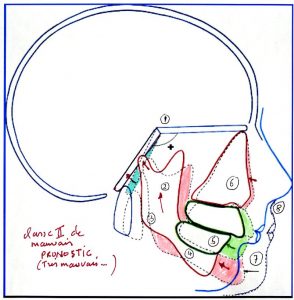

👉On doit avant tout traitement faire un diagnostic mandibulaire précis.

Par la clinique en regardant le profil ainsi que celui des parents.

Par l’analyse céphalométrique:qui étudie l’anatomie de la mandibule et ses capacités à grandir dans le temps.